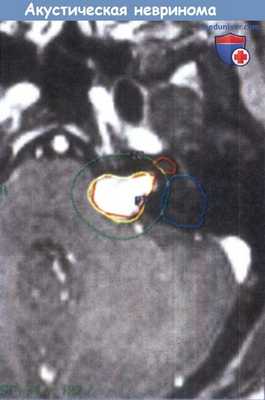

Составление протокола лечения левосторонней акустической невриномы.

Отображен объем опухоли, линии 50% и 20% изодоз. Обратите внимание на контуры улитки и полукружных каналов.

Лечение планируется таким образом, чтобы минимизировать воздействие радиации на эти структуры.